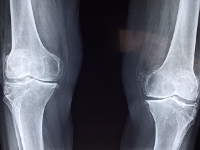

무릎 관절에 좋은 음식과 무릎 관절 관리법 등의 정보를 확인해보자. 무릎 관절은 우리 몸에서 가장 중요한 부분 중 하나입니다. 다리를 지지하고 움직임을 제공합니다. 무릎 관절은 평소에 체중과 움직임에 의해 과부하가 걸리기 때문에 연령에 관계없이 각종 질병과 부상에 취약합니다. 무릎 관절 질환에는 퇴행성 관절염, 무릎 관절염 및 무릎 관절의 연골 손상이 포함됩니다. 이러한 상태는 무릎 통증, 부기 및 움직임 제한과 같은 증상을 유발합니다. 무릎 관절 건강을 유지하기 위해서는 적절한 운동, 올바른 식습관, 적절한 체중 유지, 올바른 자세가 필요합니다. 무릎 관절 질환을 예방하고 치료하기 위해서는 정기적인 건강검진과 치료가 필요합니다.

무릎 관절에 대한 정보

무릎관절염의 원인은 다양하지만 가장 흔한 원인은 나이, 체중, 유전, 부상, 직업적 요인, 잦은 운동 등입니다.

- 나이: 나이가 들면 무릎 관절 손상이 발생할 가능성이 높아집니다. 나이가 들면 연골이 얇아지고 윤활제 분비가 감소하여 무릎 관절이 충격을 흡수하는 능력이 감소합니다.

- 체중: 과체중은 무릎 관절에 부담을 주고 염증을 일으키며 무릎 관절 관절염의 위험을 증가시킵니다.

- 유전적 요인: 유전적 요인도 무릎 골관절염의 원인 중 하나입니다. 가족력이 있으면 무릎 골관절염 발병 위험이 높아집니다.

- 부상: 무릎 관절 부상은 무릎 골관절염 발병 위험을 증가시킵니다. 특히 골절, 연골 손상 및 인대 손상은 무릎 관절증을 유발할 수 있습니다.

- 직업 스트레스: 무릎 관절에 대한 직업 스트레스는 무릎 관절의 골관절염 발병 위험을 증가시킵니다. 예를 들어 무릎을 자주 구부리거나 서 있어야 하는 작업, 장시간 서 있어야 하는 작업 등이 있습니다.

- 불규칙한 운동 : 무릎 관절에 무리한 스트레스를 가하는 불규칙한 운동은 무릎 관절에 염증을 일으킵니다.

무릎 골관절염은 위의 요인들이 복합적으로 작용하여 발생할 수 있습니다. 따라서 무릎 퇴행성관절염을 예방 및 치료하기 위해서는 건강한 식습관과 운동습관을 유지하고 무릎관절에 대한 적절한 관리가 필요하다.